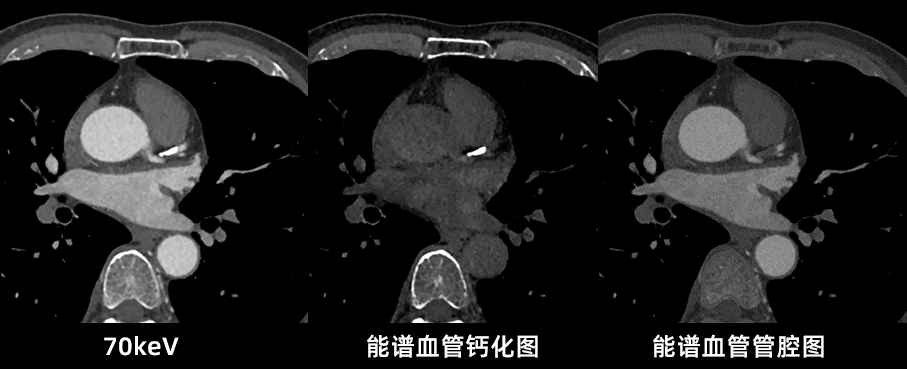

uCT SiriuX落地临床验证中,我们切身体会了这款设备的全脏器覆盖能谱成像功能,可在单心动周期内完成全心能谱采集,提供多种能谱图像类型。

例如,虚拟单能图像可优化冠脉图像对比度,有效消除血管管腔中钙化导致的晕状伪影,确保准确的血管评估;同时,基于能谱图像的物质识别技术,还可进行斑块成分分析,进一步提升诊断精度。

什么是联影ct真香预警?联影医疗双宽体双源CT大揭秘!TA竟然可以看到心脏的高清运动!_https://www.jmylbn.com_新闻资讯_第22张

什么是联影ct真香预警?联影医疗双宽体双源CT大揭秘!TA竟然可以看到心脏的高清运动!_https://www.jmylbn.com_新闻资讯_第23张